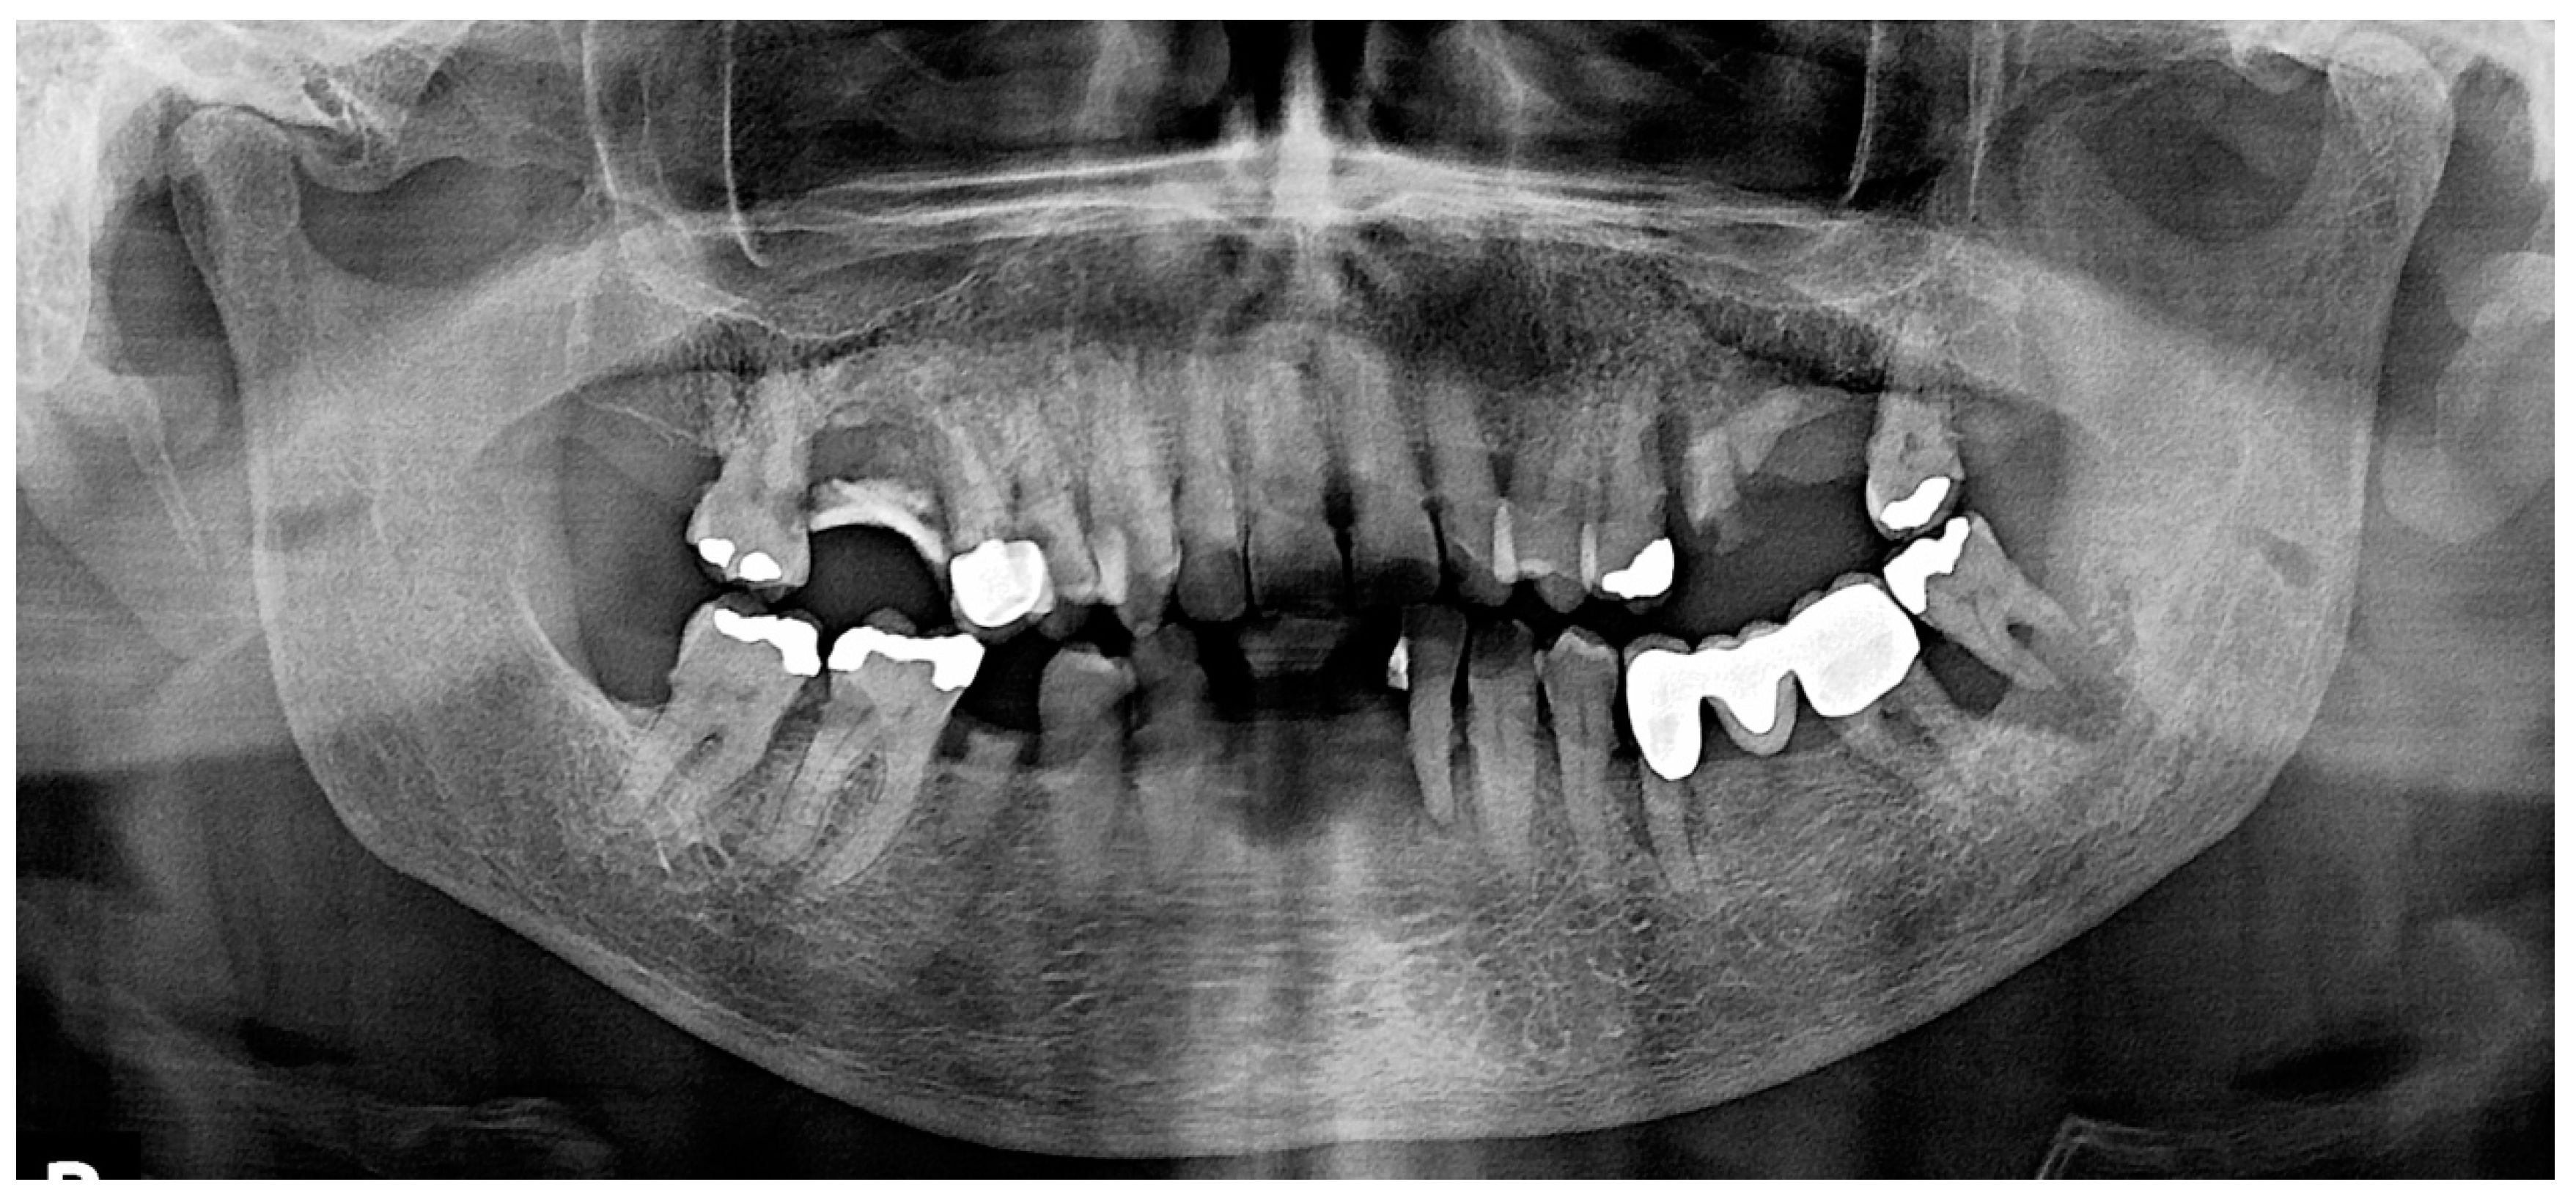

2.1. Case 1

2.2. Case 2